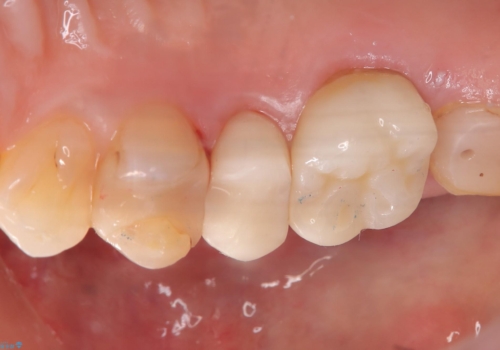

「右上4番目と5番目の間にフロスを通すといつも出血し、たまに臭いもする」という主訴で来院されました。

右上4番に歯冠色インレーが入っており、遠心側室エリアのマージン不適を認め、そこに汚れが溜まりやすい状態となっていました。